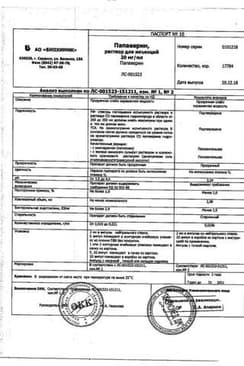

Инструкция по применению Папаверина гидрохлорид раствор 2% амп 2 мл N10

Состав препарата Папаверина гидрохлорид

Раствор для инъекций в виде прозрачной, слабоокрашенной жидкости.

1 мл

папаверина гидрохлорид 20 мг

Вспомогательные вещества: динатрия эдетат - 0.05 мг, метионин - 0.1 мг, вода д/и - до 1 мл.

2 мл - ампулы (5) - упаковки контурные ячейковые (1) - пачки картонные.

2 мл - ампулы (5) - треи картонные (1) - пачки картонные.

2 мл - ампулы (5) - упаковки контурные ячейковые (2) - пачки картонные.

2 мл - ампулы (5) - треи картонные (2) - пачки картонные.

Сертификаты